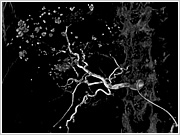

通常、血管造影は平面的な画像になりますが…

立体的に表示することが可能です。もちろんあらゆる角度から観察することができます。